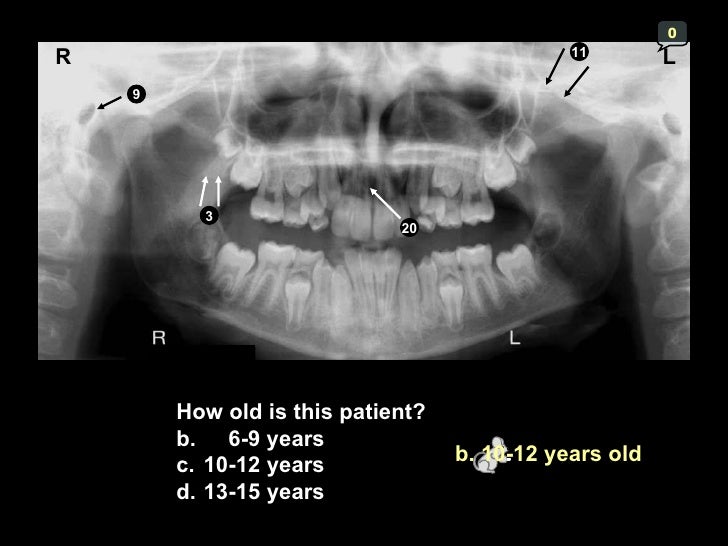

3 Radio. Anatomy.&interpert I

hamular

2015 radiology revision. Panoramic landmarks anatomical dental anatomy radiograph radiographs ppt lecture oral dentistry assistant hygiene note study tooth dentallecnotes pdf sinus uvula. 3 radio. anatomy.&interpert i